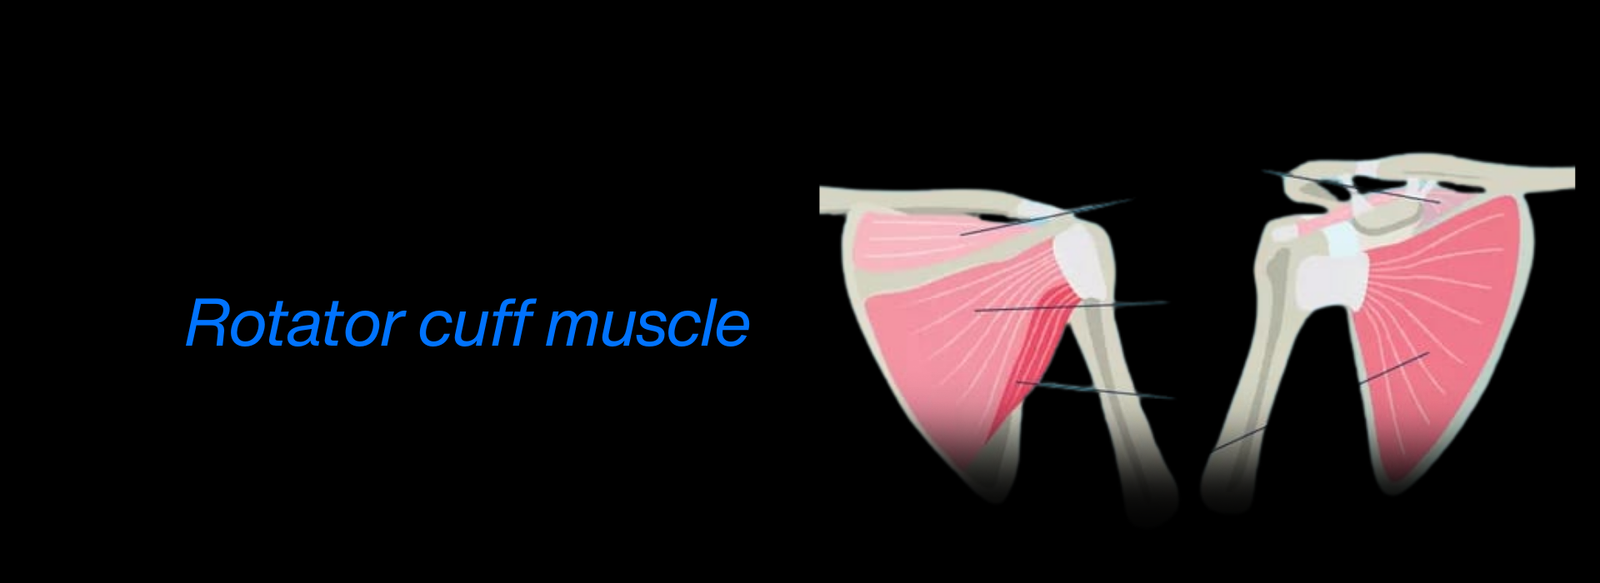

Fellowship in Arthroscopy: Expertise in minimally invasive surgery to diagnose and treat joint conditions, such as torn cartilage or ligament injuries, particularly of the knee, shoulder, and hip.